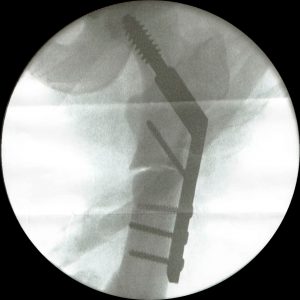

Hemos operado por segunda vez una paciente con OSTEOPETROSIS enfermedad rara que se presenta desde el nacimiento y afecta a 1 persona entre 20.000 nacimientos y 1 entre 200.000 adultos.